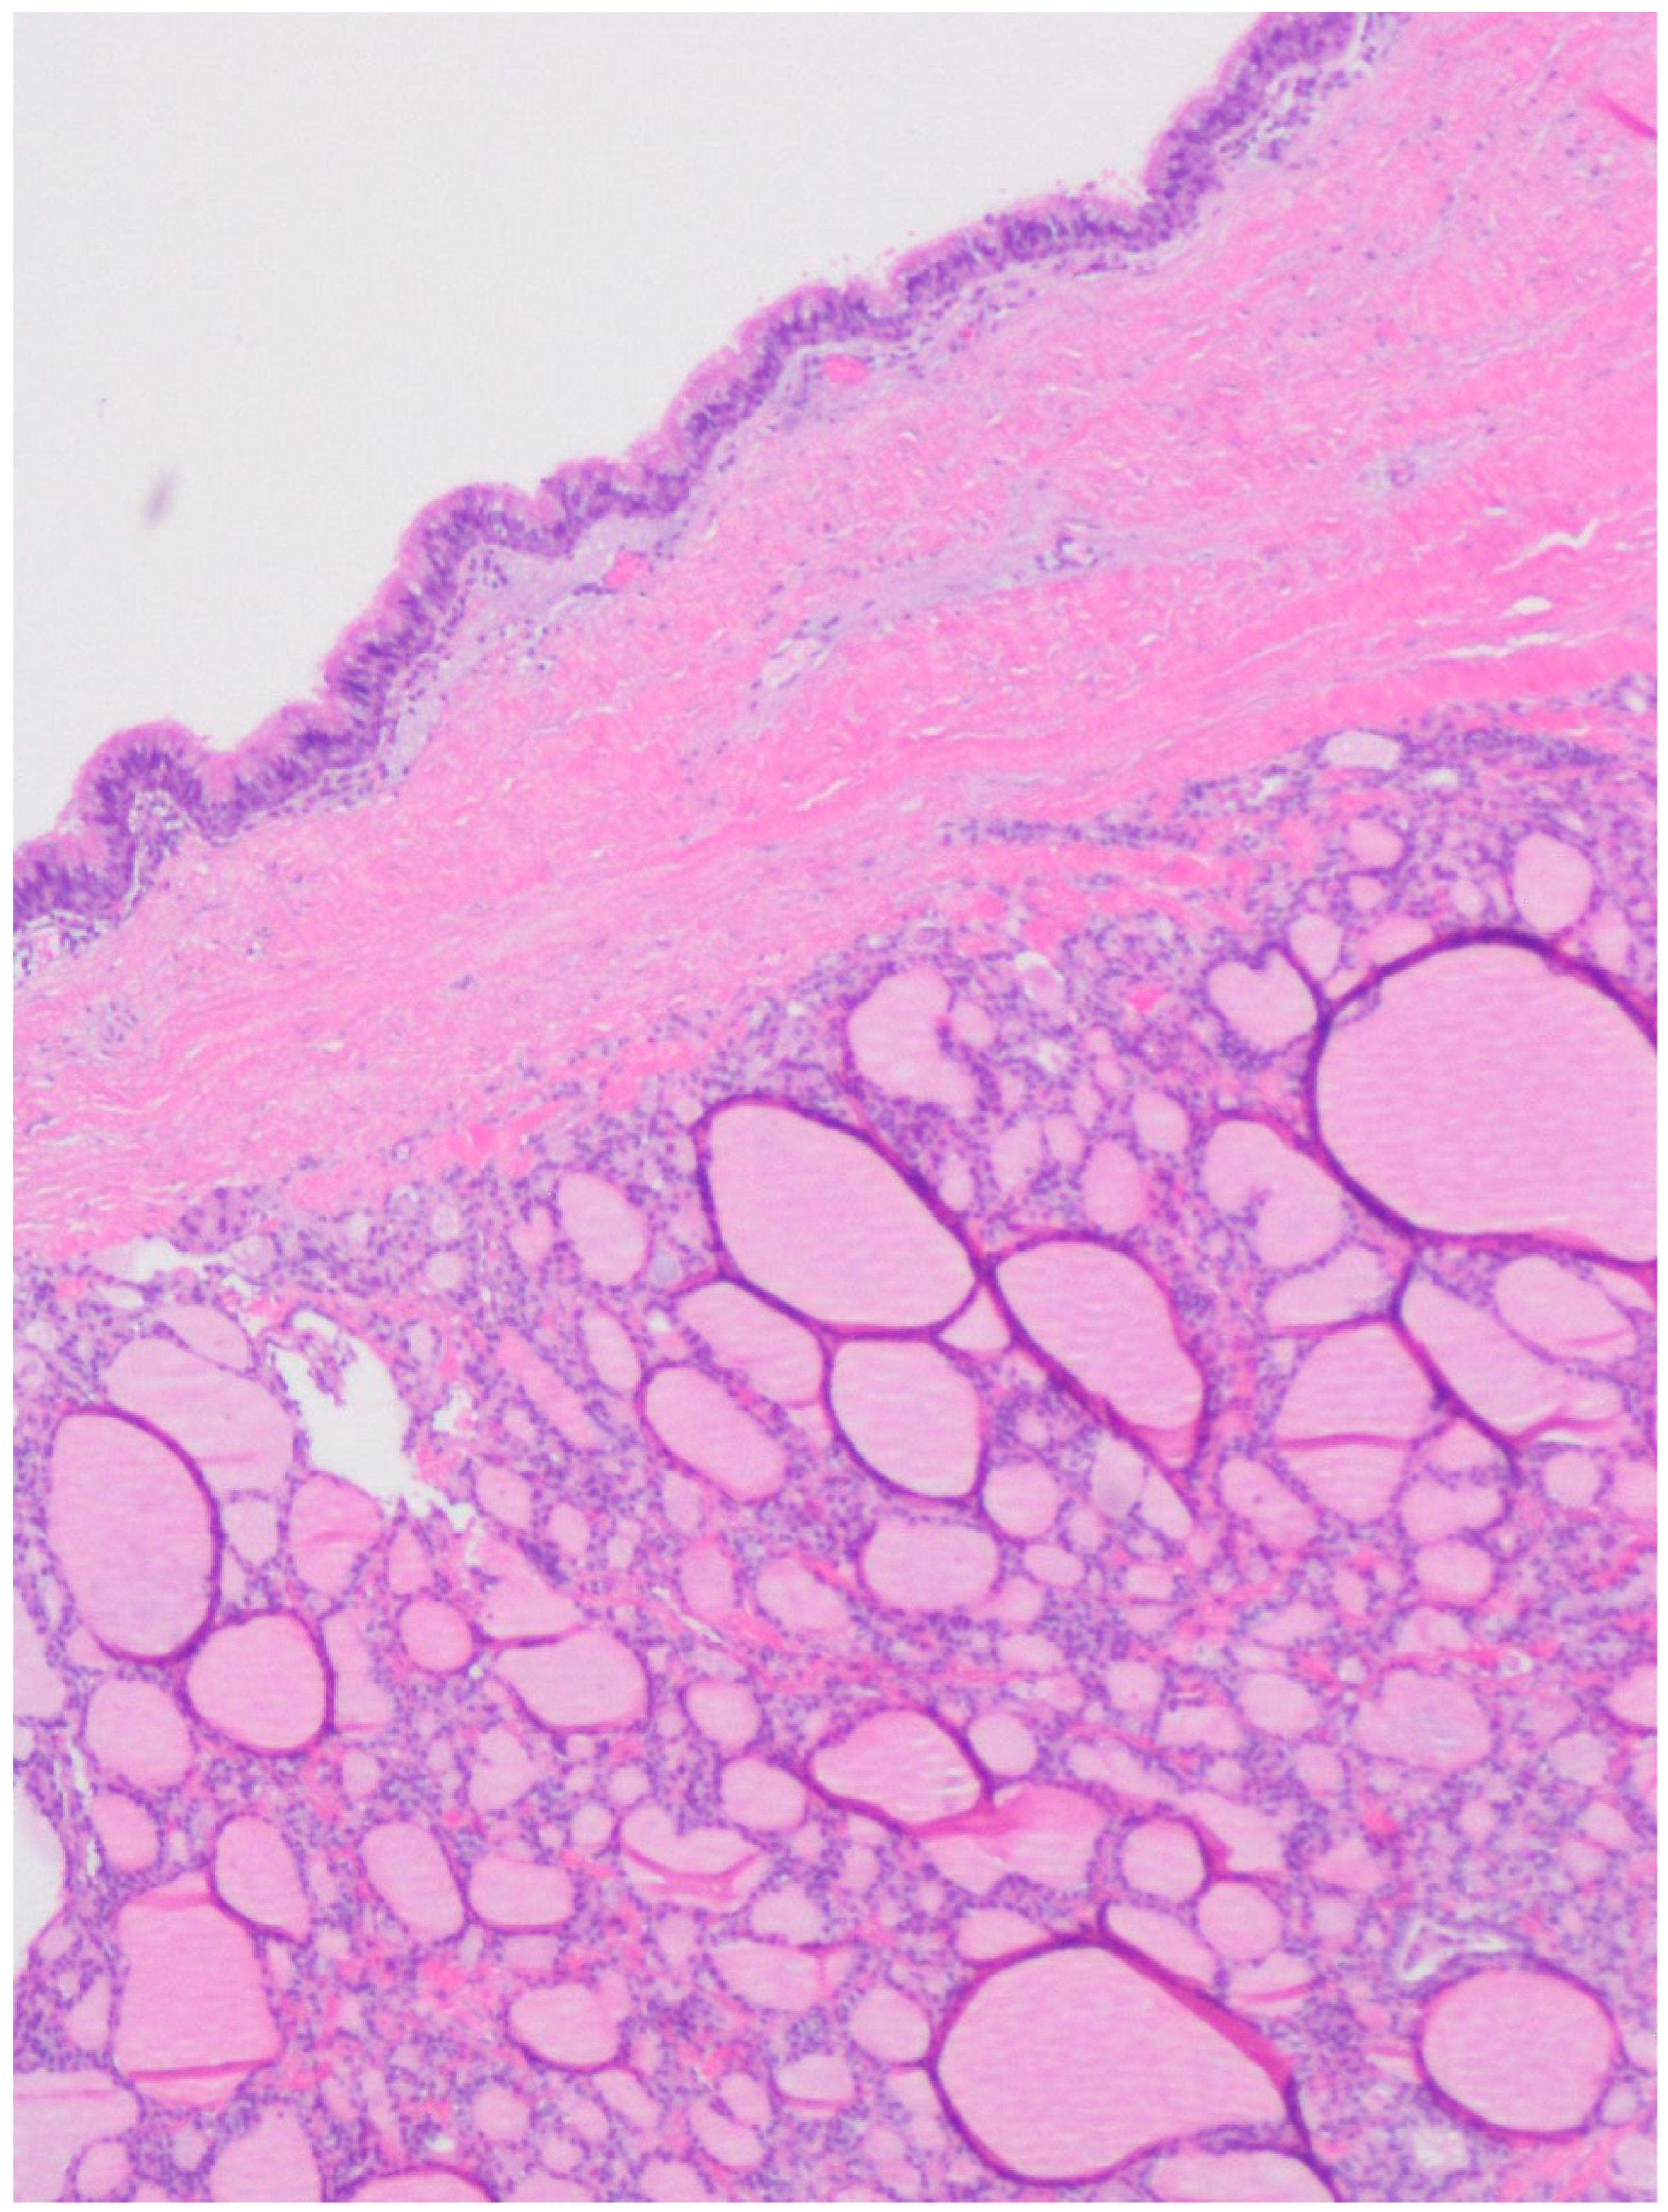

A Rare Case of a Large Composite Endometrioma–Mature Cystic Teratoma: The Importance of Surgical Treatment and Pathologic Diagnosis

2. Case Presentation